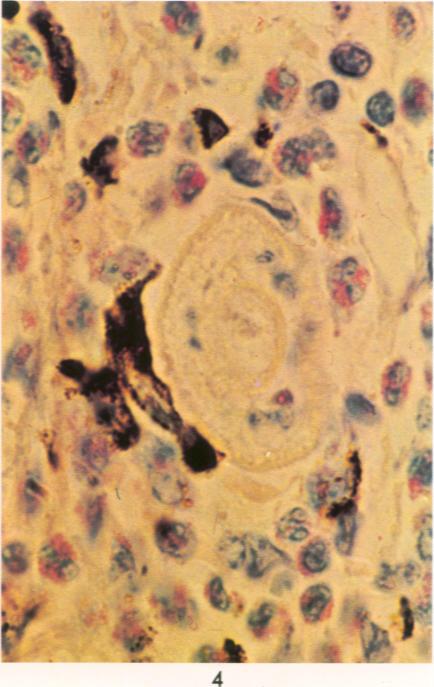

Exposure of the mouse skin to Schistosoma mansoni cercariae gives rise to acute, exudative inflammation in both normal and immune mice, but the immune response is anamnestically accelerated and is oesinophil-enriched, thereby enhancing opportunities for tegumental contact of schistosomula with host leukocytes, particularly with eosinophils. Many of the inflammatory changes occurring within the first 48 hours after exposure are due to cercarial products, e.g., "penetration tracts," but some remain demonstrable when schistosomula metamorphosed in vitro are injected intradermally and are therefore directed against the schistosomula themselves, such as the leukocyte "streaming patterns" seen in their pathways. In contrast to earlier observations in primates, cellular responses to schistosomula in the mouse lung 4 days after penetration are minimal in either normal or immune mice. Thus, immune cellular responses to schistosomula in mice are limited to an early time period after cercarial penetration and are morphologically suggestive of an antibody-mediated response rather than of delayed hypersensitivity. Our observations complement earlier evidence suggesting that antibody-mediated host leukocyte contact with schistosomula initiates the killing of challenge parasites in immune mice, with the eosinophil probably playing a crucial role.

将曼氏血吸虫尾蚴暴露于小鼠皮肤会在正常小鼠和免疫小鼠中引发急性渗出性炎症,但免疫反应会呈回忆性加速且富含嗜酸性粒细胞,从而增加了童虫与宿主白细胞(特别是嗜酸性粒细胞)体表接触的机会。暴露后最初48小时内发生的许多炎症变化是由尾蚴产物引起的,例如“侵入道”,但当在体外变态的童虫皮内注射时,一些变化仍然明显,因此是针对童虫本身的,比如在其路径中看到的白细胞“流动模式”。与早期在灵长类动物中的观察结果相反,在正常或免疫小鼠中,穿透后4天小鼠肺内对童虫的细胞反应都很轻微。因此,小鼠对童虫的免疫细胞反应仅限于尾蚴穿透后的早期阶段,并且在形态学上提示是一种抗体介导的反应而非迟发型超敏反应。我们的观察结果补充了早期证据,表明抗体介导的宿主白细胞与童虫的接触启动了免疫小鼠中对攻击寄生虫的杀伤,嗜酸性粒细胞可能起着关键作用。